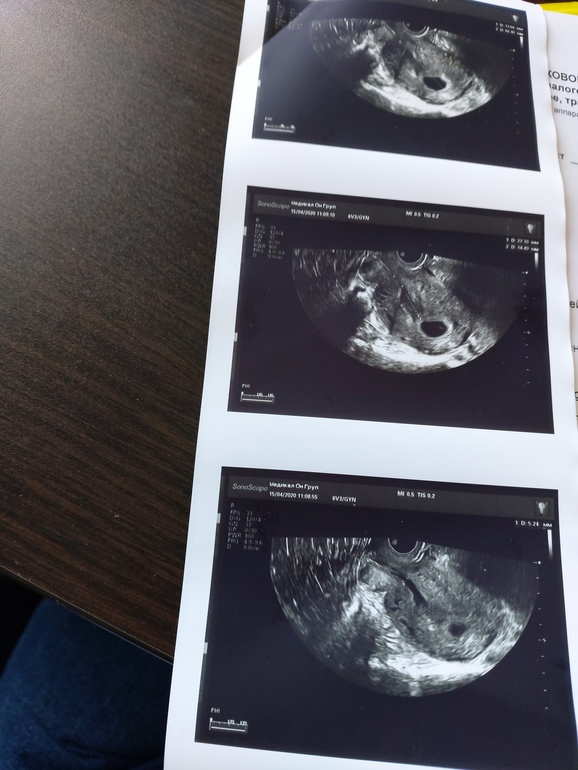

УЗИ, КТГ, доплерДевочки сегодня была на узи, слава богу нашли эмбриончика и сердцебиение! Но появились некоторые вопросы... На узи поставили угрозу и ретрохориальную гематому (к слову болей и выделений у меня ттт нет) Во втором узи написали: Плодное яйцо 30*15.2 мм ктр 4.6 мм, желточный мешок 4.2 мм. На границе с шейкой ретрохориальная гематома 27.3*14.5 мм Правый яичник:в скане анэхогенное образование размерами 16*13ммД, внутреннее содержимое однородное. Заключение; беременность 5-6 нед Гипертонус матки по передней стенке. Эхокартина ретрохориальной гематомы. Ретенционное образование правого яичника (желтое тело) А теперь внимание вопросы на первом узи желтое тело было в левом яичнике до 19 мм А теперь уже в правом яичнике желтое тело. Такое возможно? еще про анэхогенное образование написали...Первое узи если что есть у меня в дневнике. Хотела на хгч сегодня сбегать, да не успела...да и что оно сейчас уже покажет.. Вот сейчас меня смущает эта гематома и желтое тело в обоих яичниках. Может ли в данной ситуации быть многоплодная беременность? Читала что у некоторых девчонок на малом сроке ставили ратрохориальную гематому а в 12 нед узнавали о многоплодной беременности.

Ниже прикреплю узи.

Первое неделю назад , и уже сегодня![]()